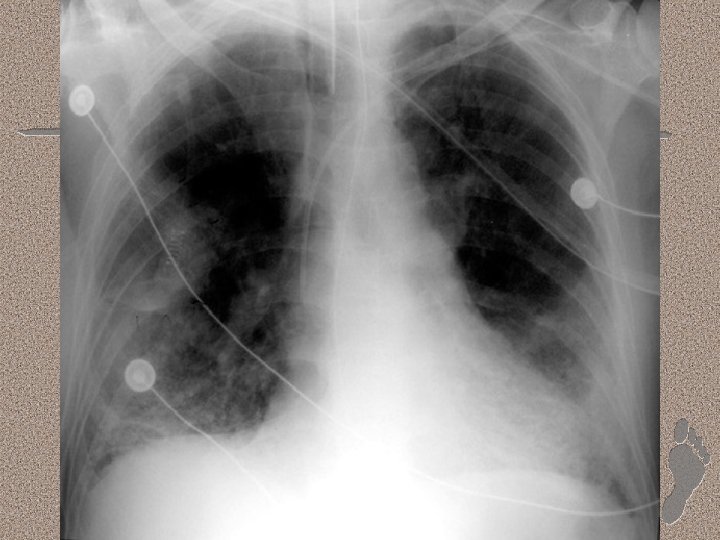

Pemeriksaan Penunjang • Laboratorium • AGD : alkalosis respiratorik pada fase awal, dan berganti menjadi asidosis respiratorik pada fase lanjut • Leukositosis (sepsis), anemia, trombositopenia (SIRS), peningkatan kadar amilase (pankreatitis) • Gangguan fungsi ginjal dan hati. • Pencitraan • • Foto dada : gambaran radioopak difus CT-Scan : pola heterogen, predominasi infiltrat pada dorsal paru (supine)